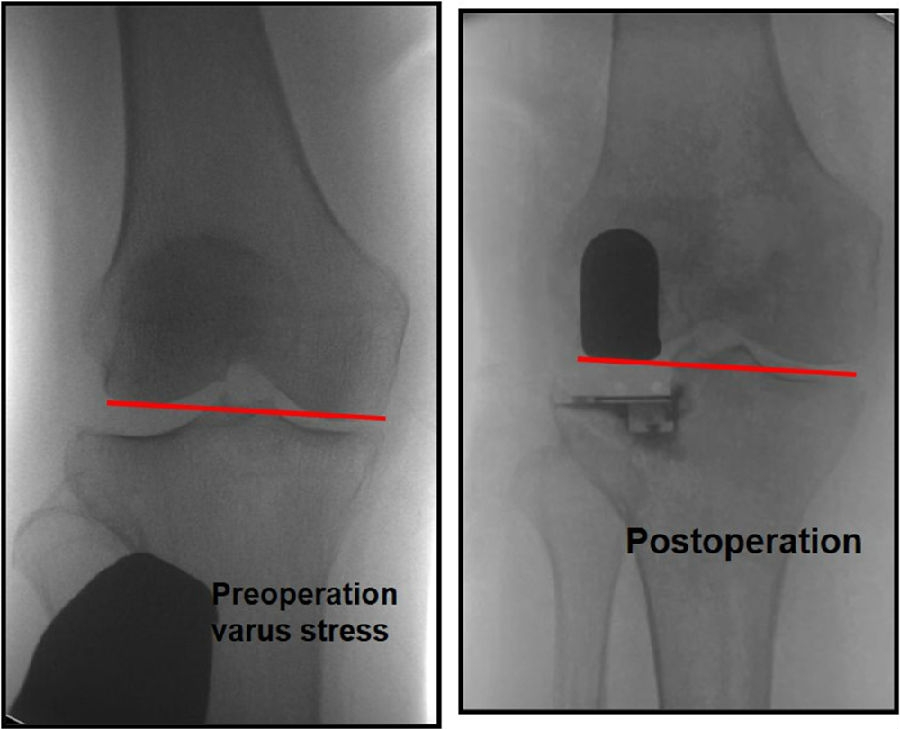

关键技术2:截骨厚度2-3mm

外侧OA多发生在股骨侧,常伴有外侧股骨髁发育不良。通常需要做内翻应力位判断外侧间隙张开程度及胫骨磨损程度。

胫骨截骨应尽可能保守,通常2-3mm即可,以利用胫骨近端皮质的强度,并可增大承载面积。

关键技术2:恢复关节线

重建关节线意义重大,因为关节线的抬高可能导致不稳定。

可能引起抬高关节线的操作:通过过度研磨股骨远端,试图匹配屈伸间隙;通过在屈曲位选择垫块厚度导致外侧间室过度填塞。

外侧间室在自然屈曲状态下松弛,将允许更厚的胫骨垫片插入,所以LUKA应在伸直位选择垫片厚度,从而达到平衡

关键技术3:理想的下肢力线

HIP-Knee-Ankle line 外翻3-5°,胫骨角10-12°

LUKA 术后畸形矫正不足,保持轻微的外翻。建议LUKA术后保留3 ~ 5°外翻。